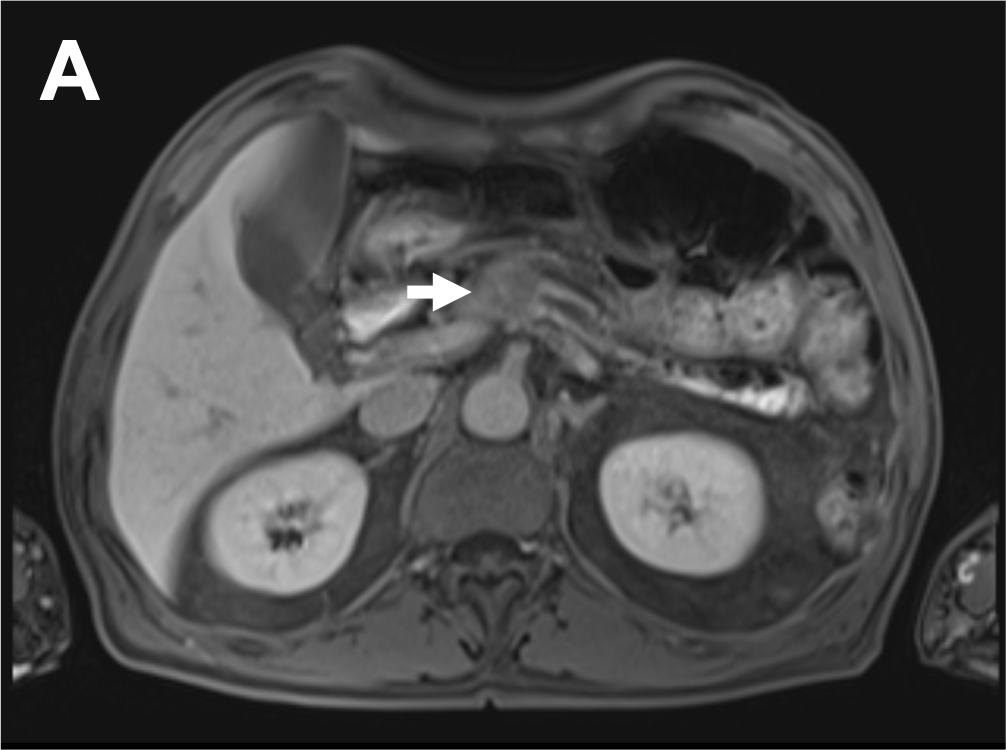

肝胆膵のCT・MRI | 本田浩, 角谷眞澄, 吉満研吾, 蒲田敏文, 入江裕之 |本 | 通販 | Amazon, 1. 診断のポイント|大腸癌肝転移の画像診断のUP to Date|GI-pedia|消化器癌治療の広場 GI cancer-net,

1. 診断のポイント|大腸癌肝転移の画像診断のUP to Date|GI-pedia|消化器癌治療の広場 GI cancer-net, 膵癌、EOB-MRIによる肝転移検索の重要性 | Search Radiology | 医療関係者向け情報,

膵癌、EOB-MRIによる肝転移検索の重要性 | Search Radiology | 医療関係者向け情報, 肝臓MRIにおける最新技術-技術解説 - GEヘルスケア・ジャパン株式会社 - inNavi Suite,

肝臓MRIにおける最新技術-技術解説 - GEヘルスケア・ジャパン株式会社 - inNavi Suite, 放射線科 | 谷津保健病院